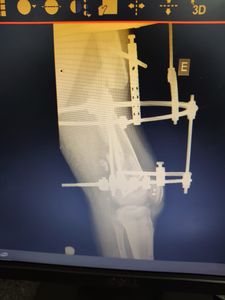

No dia 01/06/2022 sofri um grave acidente de trânsito, fraturando o fêmur esquerdo na cidade de Maringá-PR.

Fiz a cirurgia pelo Hospital Metropolitano de Sarandi pelo SUS colocando uma gaiola de ferro, chamado de aparelho Ilizarov.

A orientação médica é de que a recuperação total venha acontecer de 8 a 12 mêses.